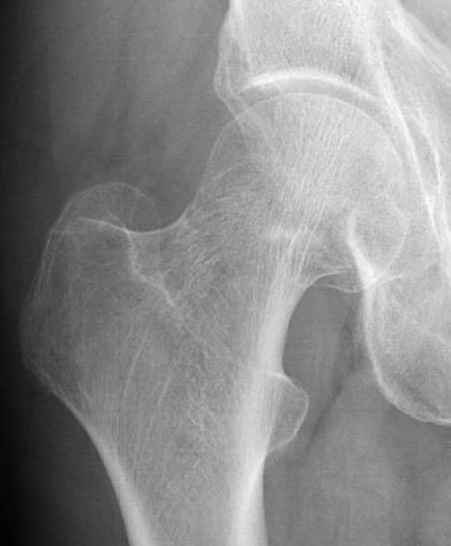

Почему неполный перелом? Я бы назвал его вколоченным!

Перелом конечно не вколоченный т.к. видно линию перелома и нет суперпозиции костной ткани.

Профилактику дальнейшего раскола неполного перелома шейки провели тремя канюлированными шурупами.

На второй день после выписки упал дома. Снимки приложены. Коллеги рекомендуют удаление шурупа и вытяжение. Что делать?